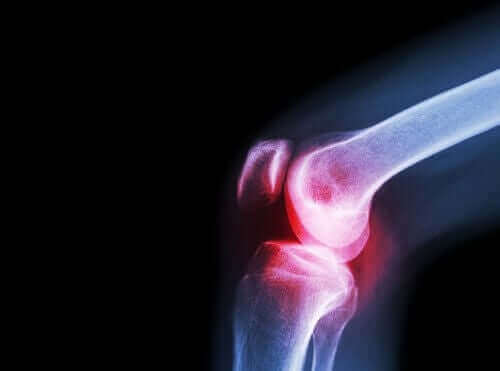

Στο σημερινό μας άρθρο θα σας μιλήσουμε για τη δράση της ασεκλοφενάκης. Πρόκειται για ένα μη στεροειδές αντιφλεγμονώδες φάρμακο, ή NSAID, το οποίο χρησιμοποιείται ευρέως για την ανακούφιση του πόνου και της φλεγμονής που σχετίζονται με τις ρευματοπάθειες. Έχει αναλγητική, αντιφλεγμονώδη, και αντιρρευματική δράση.

Οι γιατροί χορηγούν αυτό το φάρμακο σε περιπτώσεις κατά τις οποίες ο/η ασθενής χρήζει αντιμετώπισης για φλεγμονώδεις και επίπονες παθήσεις όπως πόνο στη μέση, πονόδοντο, και πόνο στις αρθρώσεις.

Επίσης, χρησιμοποιείται για την αντιμετώπιση του χρόνιου πόνου και της φλεγμονής που σχετίζεται με τις χρόνιες διεργασίες των αρθρώσεων: οστεοαρθρίτιδα, ρευματοειδή αρθρίτιδα, και σπονδυλίτιδα.